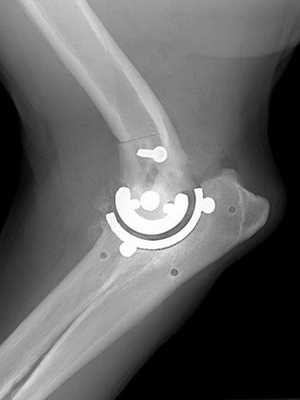

Результат операции на рентгене.

Показаниями являются фиброзный и костный анкилоз. При этом отклонении сустав частично или полностью теряет подвижность из-за патологических изменений. Причинами разрушения зачастую становятся артриты, травмы, артрозы. При множественных раздроблениях элементов, входящих в соединение, реконструкция становится невозможной. В этом случае удаляются осколки, а недостающая часть выкладывается искусственными или собственными тканями больного.

Локтевой стык способен нормально двигаться и функционировать только в том случае, если все его составляющие имеют естественные размеры и форму. Методика направлена на выполнение именно этой задачи. Сегодня выпускают готовые пластины, которыми покрывается поверхность пораженного соединения. Изготавливаются они из медицинских сплавов или полимеров. Также используются специальные пасты и смеси, которыми покрывается соединение. Эти средства проникают в поры и просветы и застывают там.